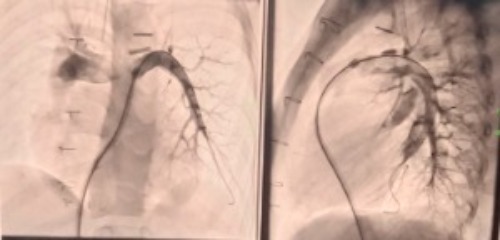

When he was only 12 days old, his entire body suddenly turned blue. The hospital had to keep baby Muhammad in the NICU and incubator for four long months. He needed complex treatment and equipment, including wires and even a sten surgery to help open up his airways.

In the future, Muhammad still needs further heart examinations and surgeries to widen his airway as he grows older.